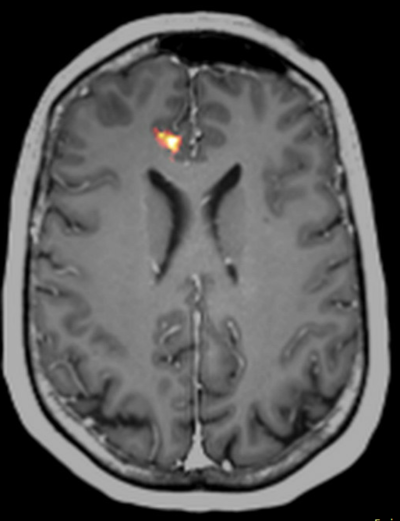

SPECT viser hjernens gennemblødning. Ved at injicere det radioaktive stof så hurtigt som muligt efter starten af et epileptisk anfald, vil stoffet aflejres hvor blodgennemstrømningen var størst på det tidspunkt og det bliver siddende noget tid, så området kan påvises på en SPECT-scanning som udføres timer efter anfaldet er ophørt. Da blodgennemstrømningen generet er høj i hjernen kan området tydeliggøres ved at subtrahere en ictal SPECT med en inter-ictal SPECT. (SISCOM = Subtraction Ictal SPECT co-registered to MRI).